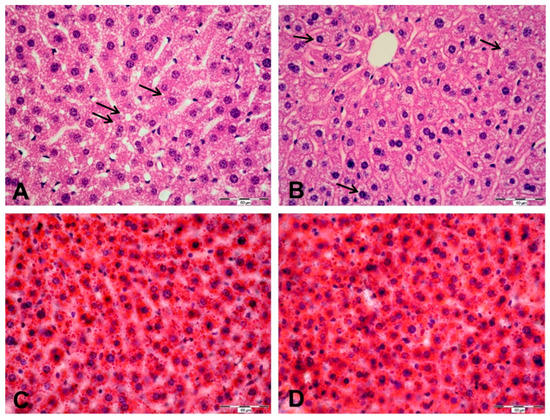

2.5. Histological and Ultrastructural Changes